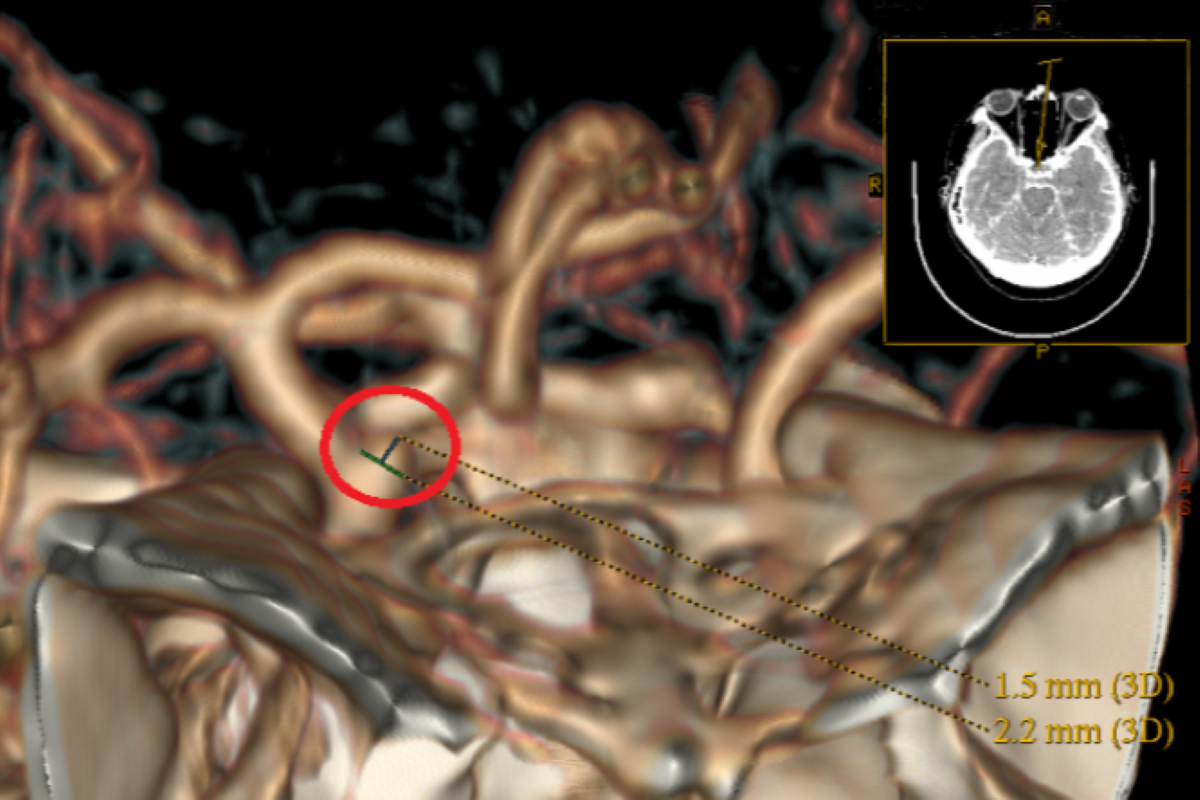

台北慈濟醫院神經外科醫師張迪生以電腦斷層血管攝影確認,其內頸動脈與眼動脈之間潛藏一顆2.4毫米大的水滴型動脈瘤,而在手術開始之際,動脈瘤便發生2次破裂,醫療團隊隨即將林女士轉入加護病房觀察。經過兩週密切照護,林女士的腦壓逐漸穩定,張迪生再次進行開顱及動脈瘤夾閉手術,後續配合腦室腹腔引流及顱骨成形手術讓腦壓恢復穩定並復位。術後至今,林女士神經學預後良好,重新回到日常生活。

臨床上,動脈瘤主要利用電腦斷層血管攝影來診斷,治療上以開顱手術為理想選擇。而透過夾閉手術,動脈瘤的復發風險極低,但預後仍取決於病人在急性期是否能順利度過血管痙攣、水腦症與癲癇等階段性挑戰,因此術後仍需密切追蹤,必要時予以腦脊髓液引流及藥物控制,同時搭配妥適的復健與生活照護。